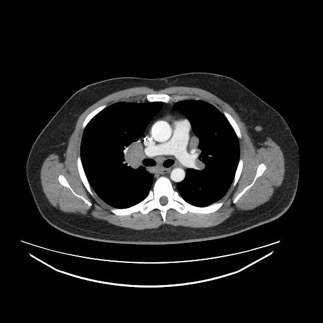

Diagnostic tests. Results of chest radiography (Figure 2) and computed tomography (Figure 3) revealed bilateral hilar adenopathy. The angiotensin-converting enzyme (ACE) level was found to be high. Results of a complete blood cell count, a basic metabolic panel, and liver function tests were normal, as were the erythrocyte sedimentation rate and the C-reactive protein level.

Figure 2. Chest radiograph showing hilar adenopathy.